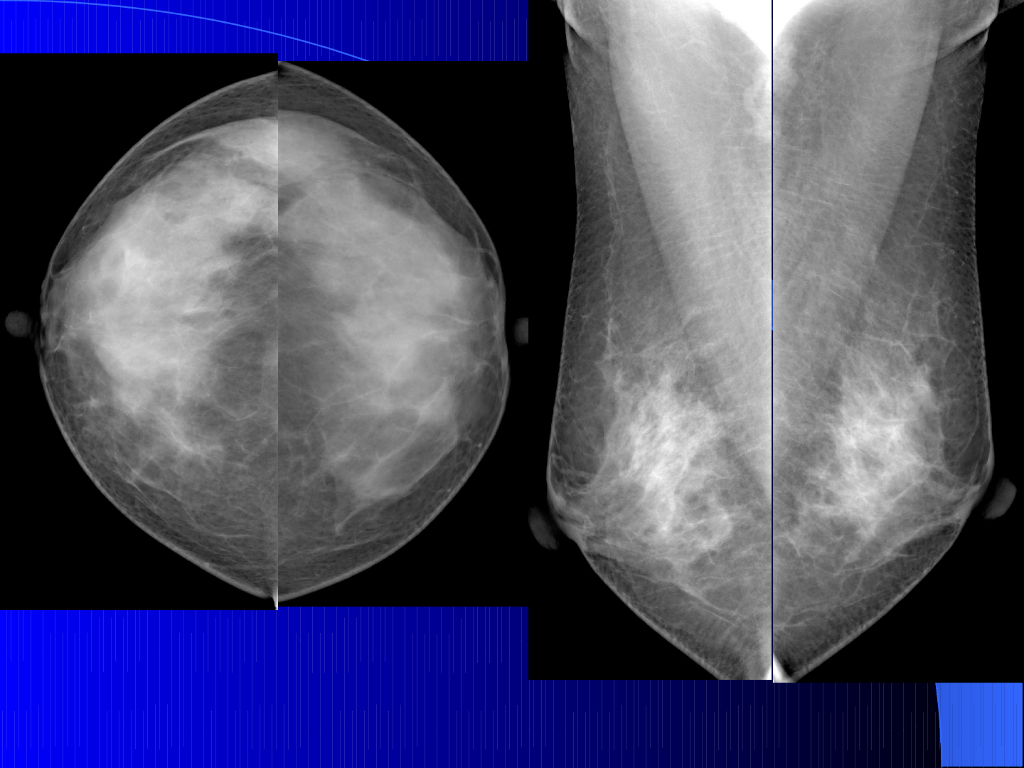

《放射诊断学》演示文稿-乳腺规范化诊疗及报告规范.pdf